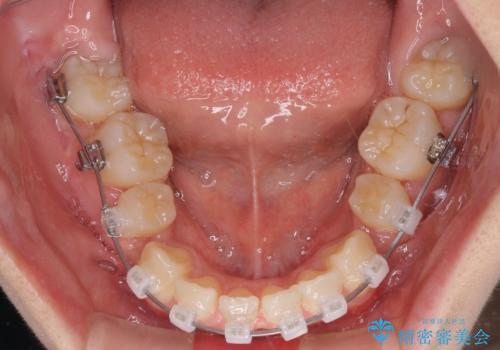

- 矯正装置

- クリアブラケット